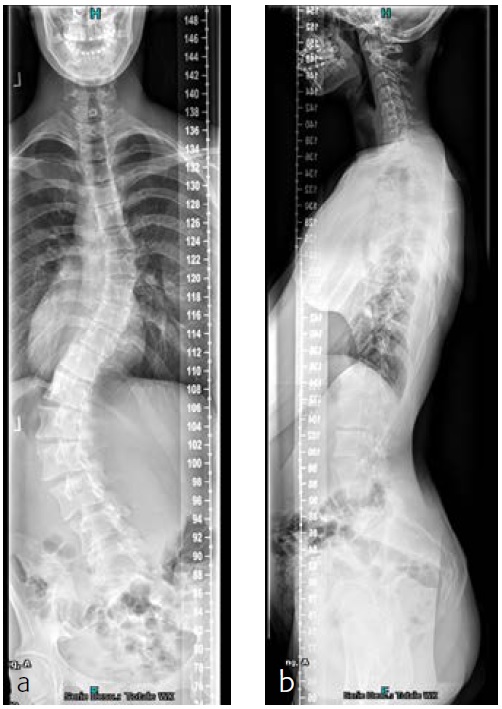

The patient was known and under orthopedic control for a Lenke 5C-type AIS since 2009. Initial treatment with a Boston Brace failed to halt progressive growth, and curve progression became apparent beyond surgical treatment threshold (Fig 9). Bending FS showed TL correction 58 -> 30 (plm 50%). MT correction 43 -> 16 (plm 35%) (Fig 10). The patient was referred to our hospitalfor logistics regarding surgical planning.

After her visit to our clinic, she was planned for surgical correction of the deformity from T5L4 (Fig 11). Surgical procedure with IONM (TC-MEP) postoperative epidural analgesia with the catheter tip at T8. She was mobilised the first postoperative day (Fig 12) and discharged the fourth day after surgery. The patient returned for her 6-month follow-up without any complaints. Limitations are in line with our advice (no sports for 6 months postoperatively). She has no pain and uses no medication.